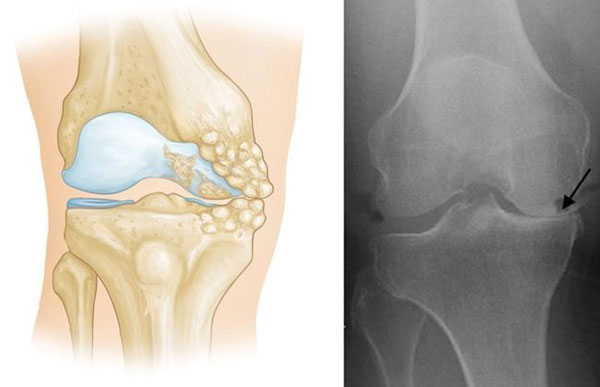

Knee osteoarthritis may occur in any one of the three compartments that make up the knee joint. The medial compartment is by far the most frequent site of osteoarthritis of the knee, with the disease occurring less frequently in the lateral compartment. Isolated patellofemoral osteoarthritis is even more uncommon.

Patients with uni-compartmental knee arthritis have osteoarthritis in only one section or compartment of the knee. In cases where non-operative therapies do not provide sufficient symptom relief, surgeons can remove damaged cartilage and bone in the diseased area only, while preserving the ligaments that help support the knee joint as well as the cartilage in the unaffected areas of the knee.

The Uni Knee replacement takes the place of the damaged area of the knee, leaving the other compartments intact.